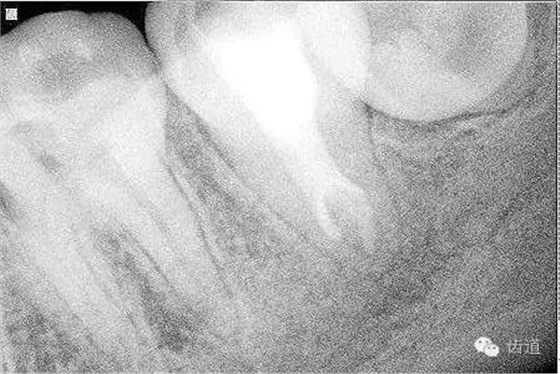

2. 術(shù)前X片

可見(jiàn)37根管影像清晰,根中上三分之二粗大,根尖三分一分為近遠(yuǎn)中兩根管,形態(tài)均呈弧形,根尖周膜連續(xù)性中斷,根尖周透射影明顯